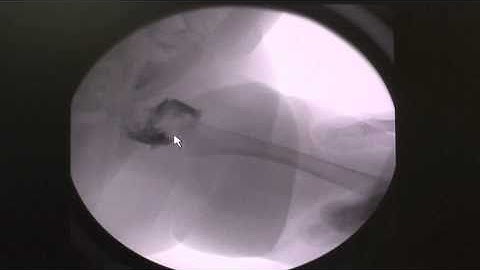

Arthrogram in older child with a successful hip joint reduction